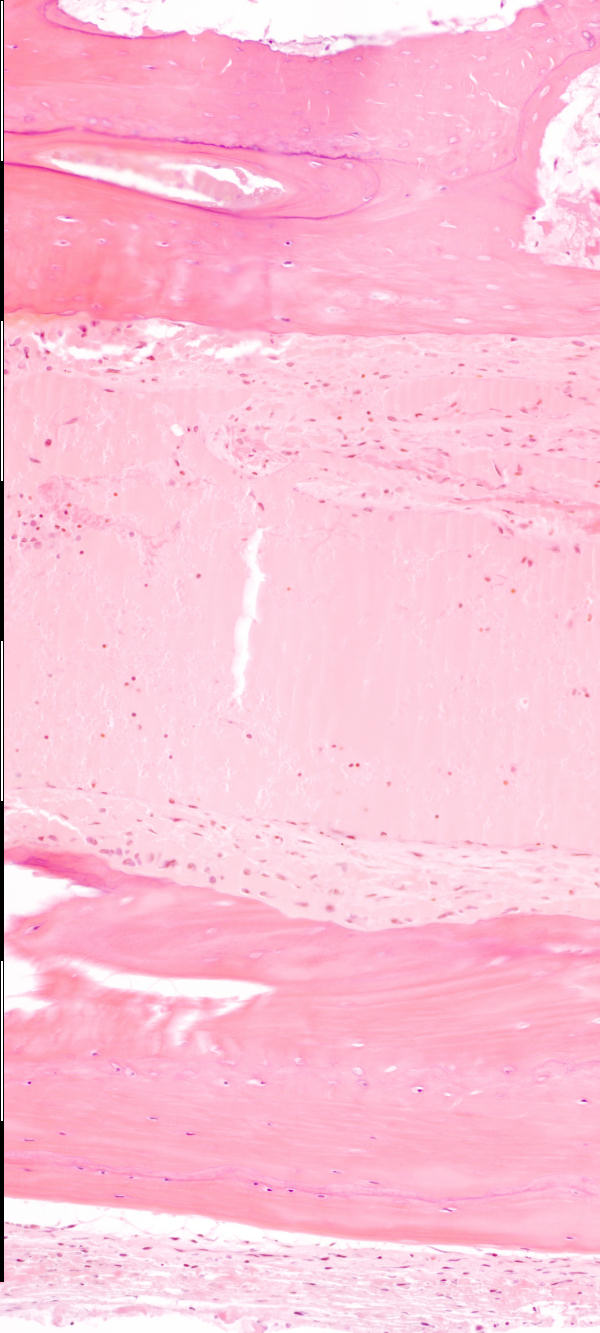

Medium magnification of immature bone

Beenhermoduleringseenhede / Bone-remodeling units Groeilyne / Growth reversal lines Osteosiete / Osteocytes